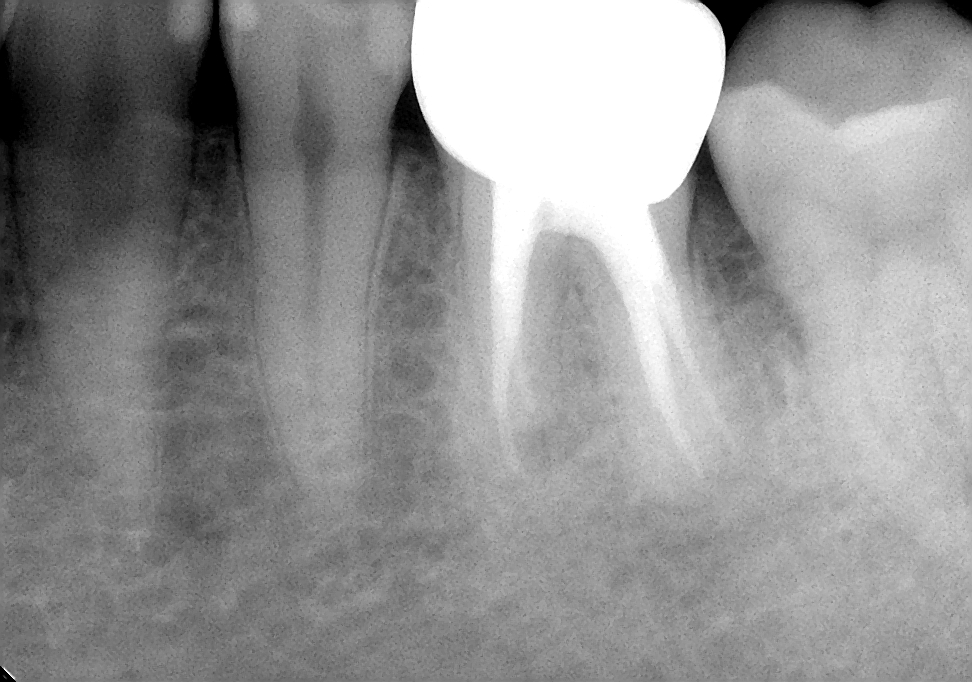

今回の患者様は、もうかれこれ10年の長いお付き合いの患者様です。来院のきっかけは、むし歯の治療でしたが、レントゲン写真から以前の神経を取った治療を行ったところに新たな病気が出来ていました。患者様の希望もあり、根管治療とその後の被せ物の治療も行いました。

約10年前のその当時を思い出してみると、私はマイクロスコープを使った根管治療を始めたばかりの頃だったと思います。いろいろなセミナーに通い、技術を習得していました。

その習得したばかりの技術を用いして何とかこの歯を保存できないかとがんばっていたことと思われます。

現在と比べると、使用している器具や材料では違いはありますが、治療において守るべき基本的なところは変わっておらず、基本に忠実な治療をしたのではないでしょうか。